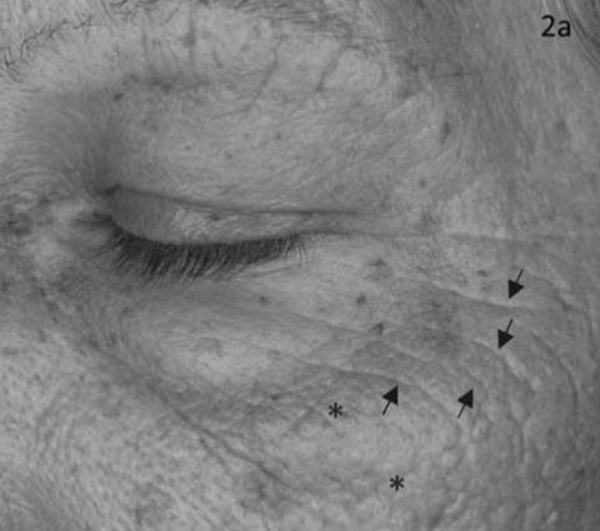

На фотографиях представлены два пациента, фотографии сделаны до (слева) и после приема добавки Q10 (справа). Стрелки указывают на уменьшение морщин. По мнению дерматологов, Q10 сделал кожу мягче и уменьшил количество мелких морщин.